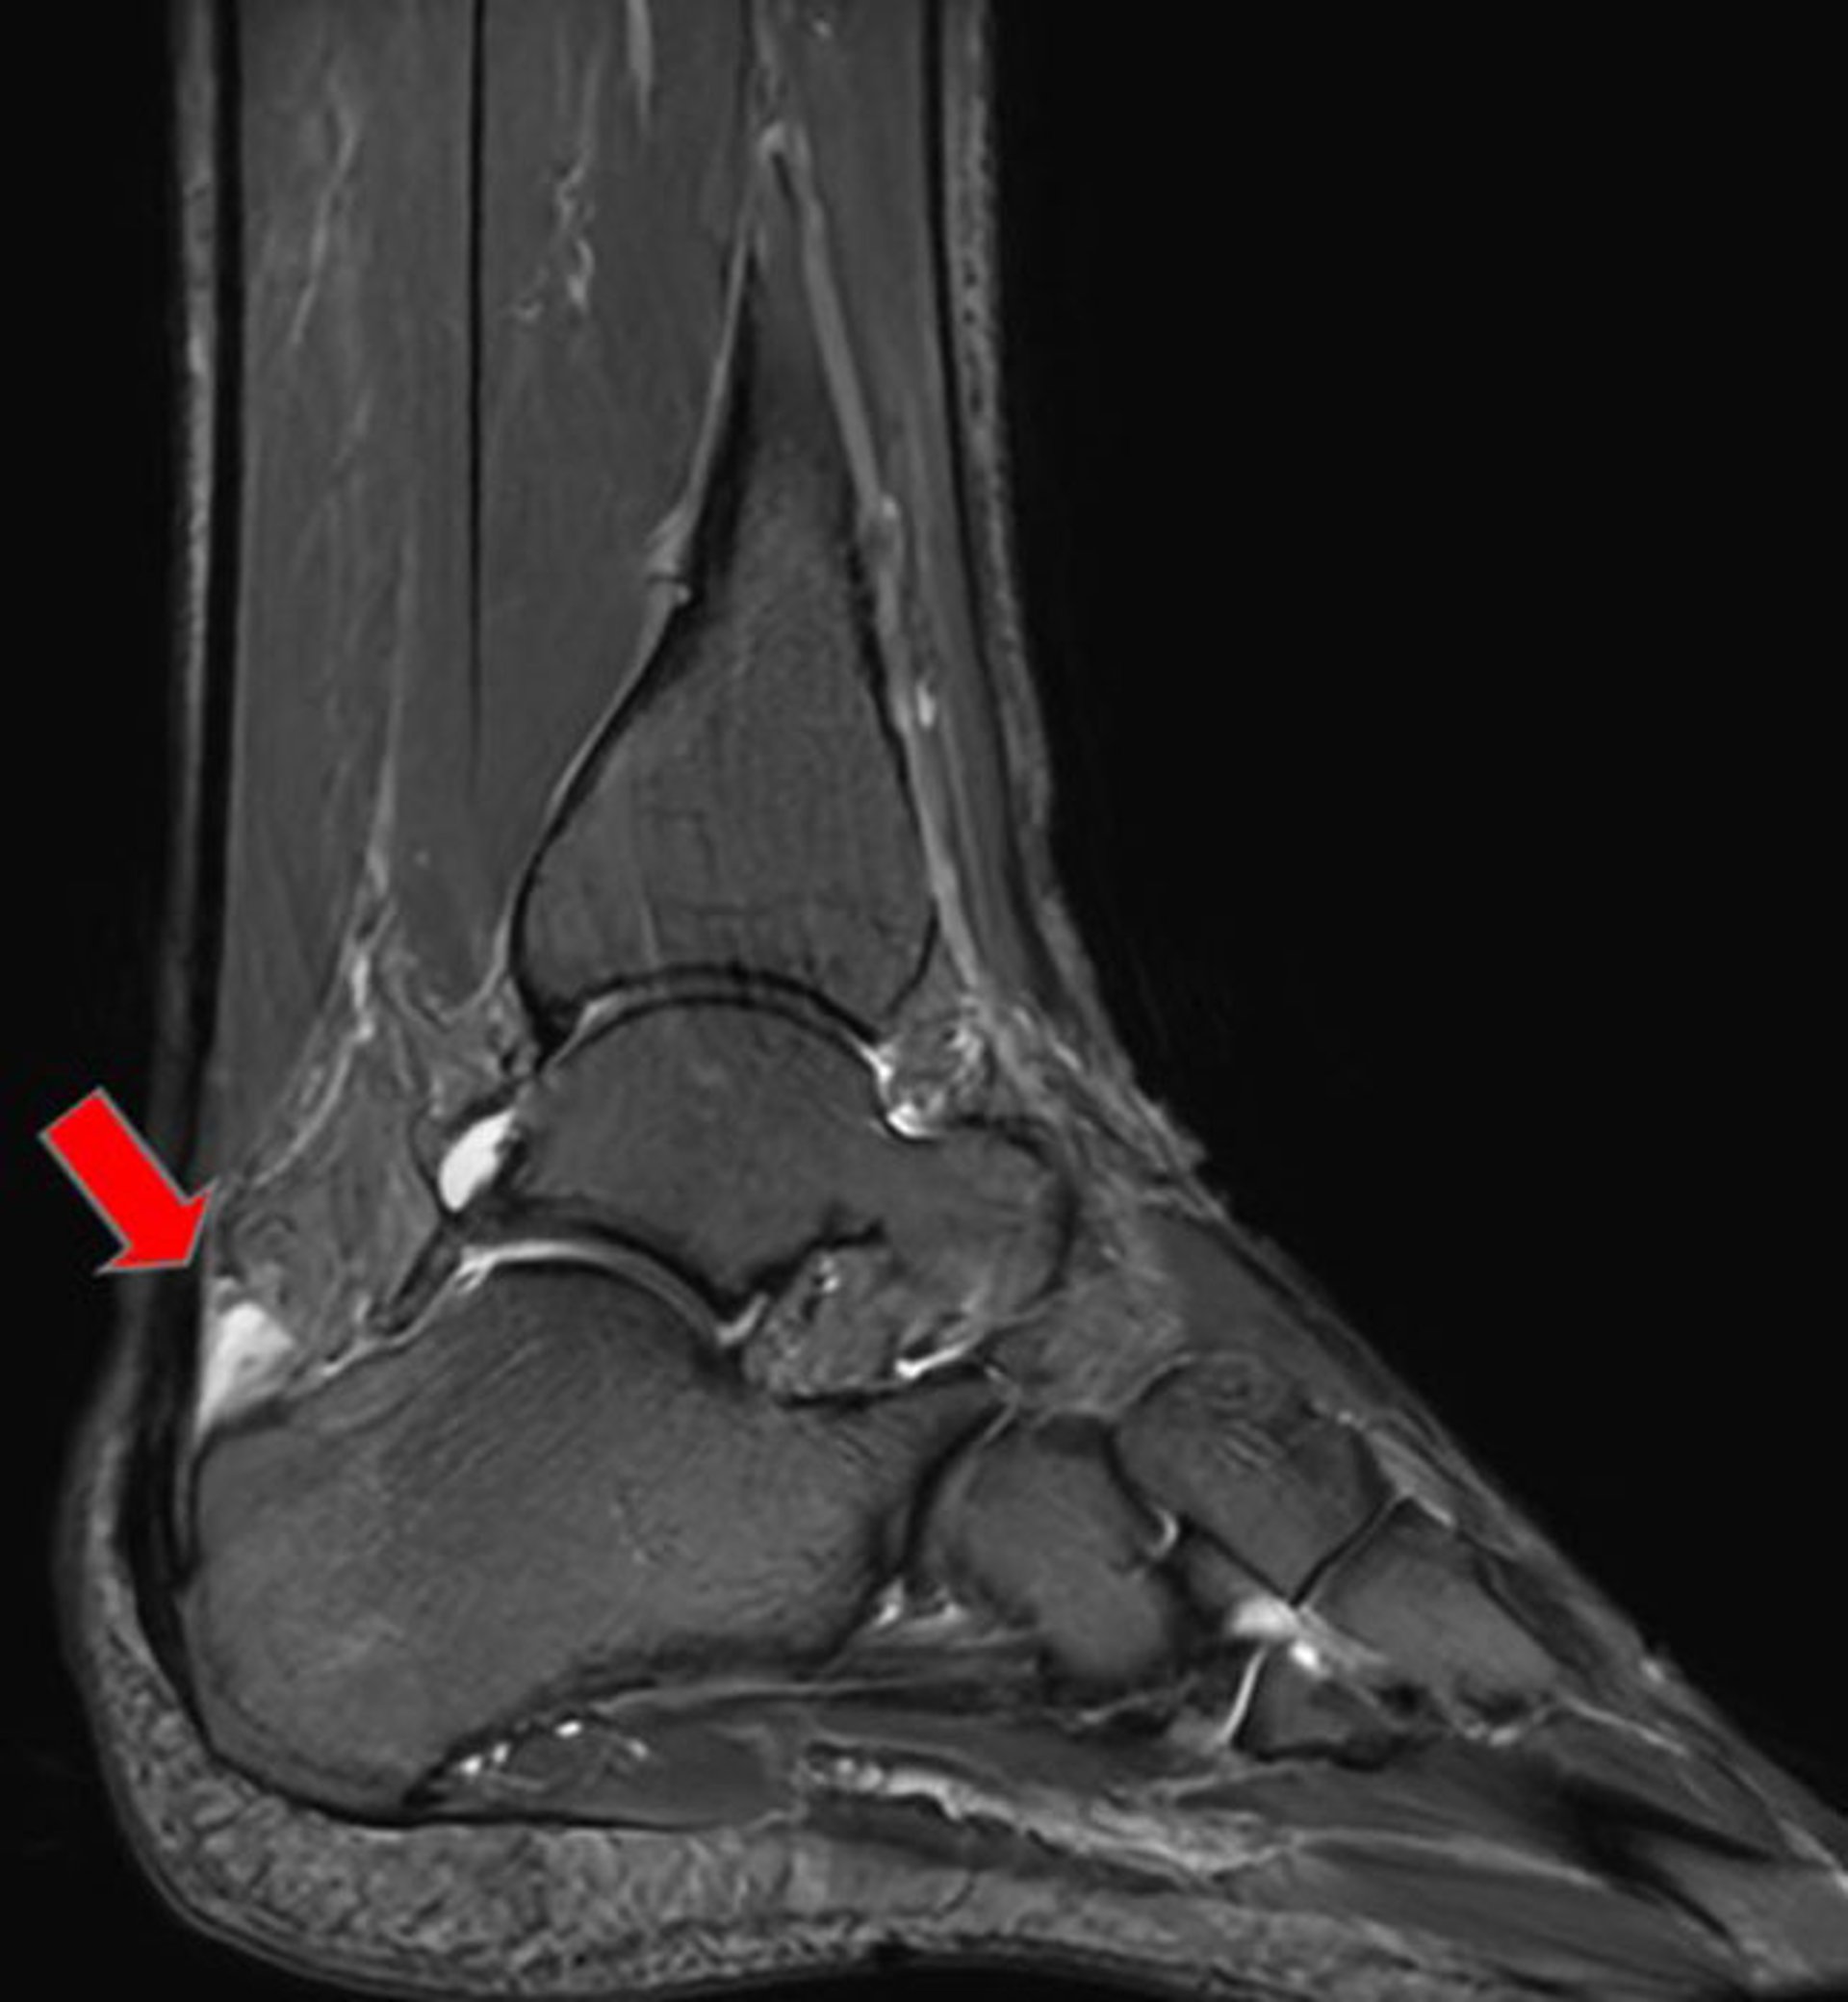

This sagittal T2 MRI shows an anterior Achilles tendon bursa (arrow).

Image courtesy of James C. Connors, DPM.